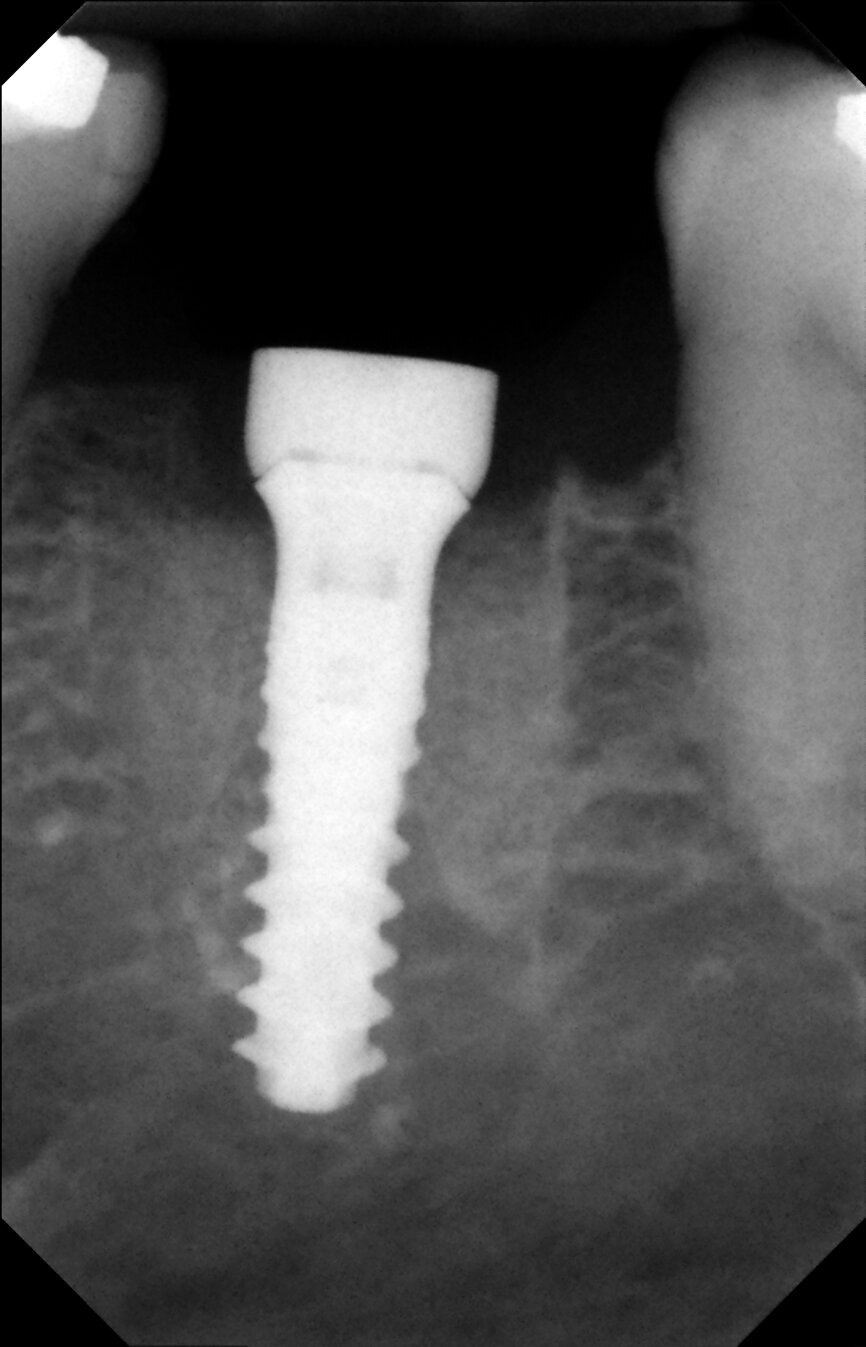

Fig. 17: Periapical radiograph after implant placement.

Fig. 26: Final outcome radiograph.

Fig. 29: One-year follow-up radiograph showed peri-implant stability.

It was possible to verify solid interradicular bone availability (Fig. 5), extending further the limits of the root apices and allowing for a centrally oriented osteotomy. The implant bed preparation started with the use of a needle drill at 800 rpm, followed by the ⌀ 2.2 mm and ⌀ 2.8 mm drills (Figs. 6–10). The implant was placed with the use of ratchet and torque control, reaching the desired final position at a 50 N cm torque value (Figs. 11–13). The socket was then augmented with bovine-derived bone substitute impregnated with advanced platelet-rich fibrin (A-PRF) and finalised with sutures to keep the A-PRF application immobile, and a 3 mm healing abutment was placed (Figs. 14–17).

From a clinical perspective, the immediate placement and function were very well indicated as they could be verified through the gingival margins and health, and bone levels throughout the healing phase, and final and one-year follow-up images (Figs. 24–29).